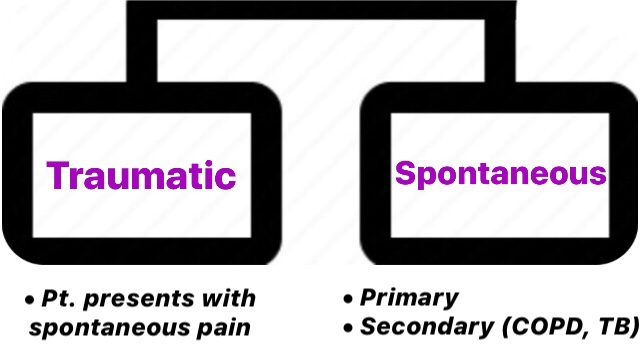

8) PNEUMOTHORAX

➡️ Pneumothoraces are collections of gas within the pleural space. If the pneumothorax is under pressure, it is called a tension pneumothorax.

- primary spontaneous pneumothorax: discharge with early outpatient follow-up and advised to return if symptomatic

- secondary pneumothorax: observe with high-flow oxygen therapy and consider intervention